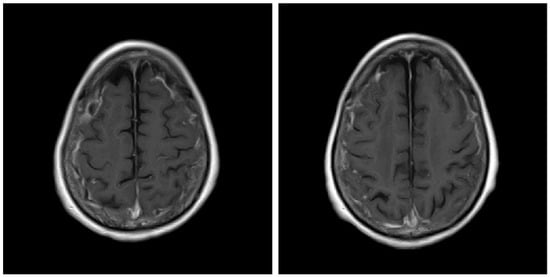

The patient was also tested for infectious diseases but was negative for herpes simplex virus 1, varicella-zoster virus, cytomegalovirus, Epstein–Barr virus, hepatitis B virus, hepatitis C virus, and cryptococcus. Differential diagnosis of non-infectious granulomatous meningitis includes sarcoidosis and tuberculosis. However, there were no other clinical findings, such as bilateral hilar lymphadenopathy, that were indicative of sarcoidosis. Moreover, she had no history of tuberculosis, and a current tuberculosis infection was excluded because no mycobacteria were detected in the CSF; her T-SPOT-TB was negative. Therefore, the patient was diagnosed with rheumatoid meningitis. Prednisolone sodium succinate (40 mg/day; 1 mg/kg/day) was administered by infusion on day 1 to day 9 after admission, and her consciousness level gradually improved. No antibiotics were used. MRI was performed on the 10th day of hospitalisation and showed that the high signal that had been observed in the previous FLAIR sequence had almost disappeared, except in the left frontal region. In contrast, no change was observed in diffuse hyperintensity (T2-WI, FLAIR) of cerebral white matter showing leukoaraiosis (Figure 2 and Figure 3). Since the level of consciousness had improved, her medication was changed to prednisolone 30 mg/day on Day 10 of hospitalisation. On Day 16, her consciousness level recovered to E4V4M6 on the GCS, and she was transferred to another hospital.

Figure 3.

T2-weighted (T2WI) magnetic resonance imaging scans of the brain. Before treatment (A,B) and after treatment (C,D).